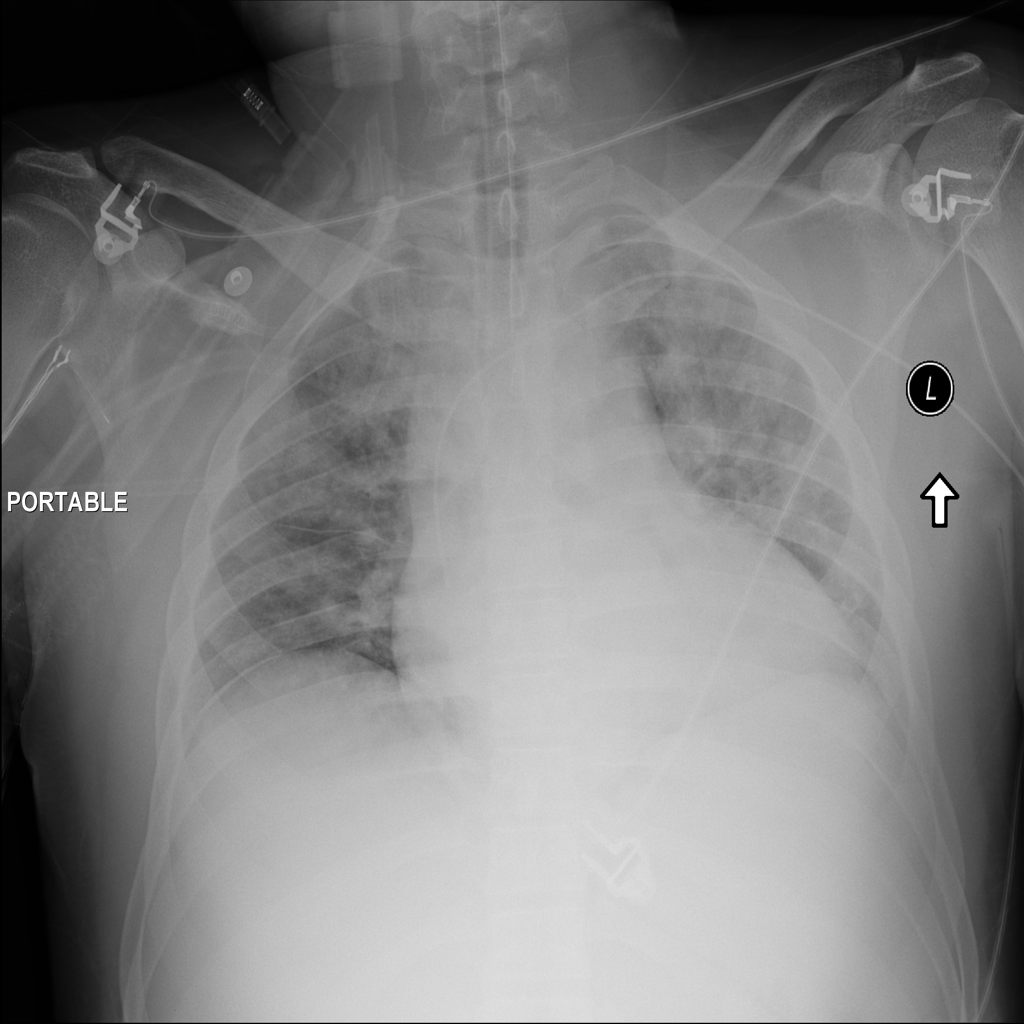

PAT-E828 · IMG-005Edema

PAT-E828 · IMG-005

AP